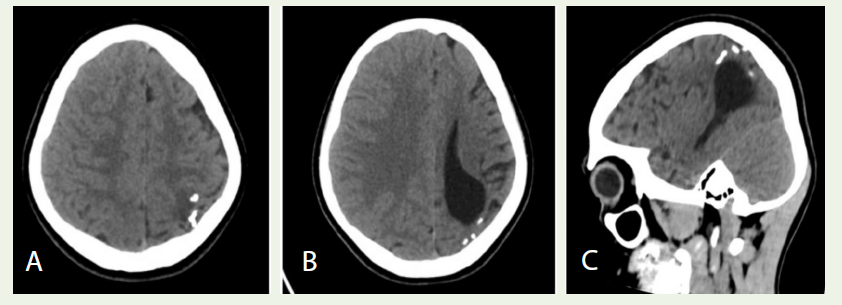

Case 3: A 13-year-old girl with a facial port-wine stain had left parietal gyriform calcifications and hemiatrophy on CT [Figure 3A-C], diagnosing Sturge-Weber syndrome.

Case 3: Sturge-Weber Syndrome (Left Cerebral Hemisphere):

Clinical presentation: A 13-year-old girl with a congenital portwine

stain on the le side of her face presented with multiple seizures

(first at 9 months of age). Neurological exam was otherwise normal.

The facial capillary malformation suggested a neurocutaneous

syndrome.Imaging findings: Non-contrast cranial CT showed classic signs.

Gyriform (tram-track) calcifications were present in the cortex of

the left parietal lobe [Figure 3A-C]. There was marked atrophy of

the left cerebral hemisphere, with cortical thinning and ipsilateral

displacement of the falx [Figure 3B]. These findings reflect chronic

leptomeningeal vascular malformations.

Diagnosis: The clinical and imaging findings are characteristic of

left-sided Sturge-Weber syndrome.

Figure 3: A: Axial CT image showing gyriform (Tram-track) calcifications in the left parietal cortex. B: Axial CT image showing atrophy of the left cerebral hemisphere with ipsilateral falcine displacement. C: Sagittal CT image demonstrating the left parietal cortical calcifications (Tram-track sulcal calcifications).